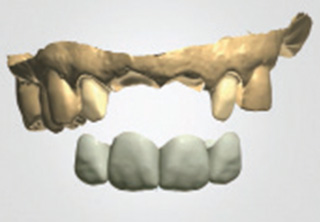

청담네오플란트 원데이 임플란트

하루만에 발치와 임플란트 식립을 동시에!

일반적으로 살릴 수 없는 치아를 발치하면, 2~3개월의 잇몸뼈 회복기를 거친 후 임플란트를 식립하게 됩니다. 하지만 잇몸뼈의 소실이

심하지 않은 경우 임플란트의 전체 치료기간 단축과 환자분의 불편감을 최소화하기 위해 내원 당일 발치 및 임플란트 식립을 진행할 수 있습니다.

필요에 따라 치조골 이식이 필요할 수 있으며, 가능한 경우 당일 임시 보철물 장착까지 해드려 심미적 기능을 회복할 수 있습니다.

발치 후 임플란트를 식립하고, 바로 임시 보철물을 제작함으로써 일상생활에서 불편감을 최소화할 수 있습니다.